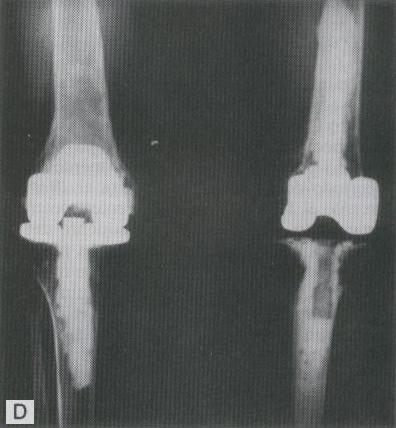

RECAMBIO TOTAL DE RODILLA CON PROTESIS BILATERAL

ESQUEMA DE UN RECAMBIO TOTAL DE LA RODILLA CON PROTESIS